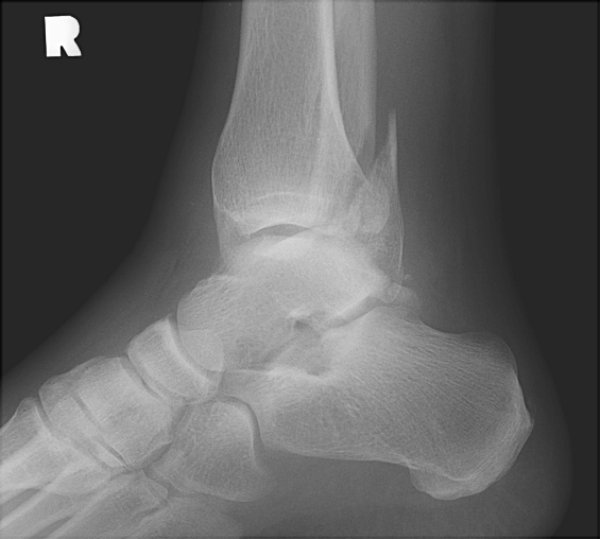

Return to Weber C Fracture